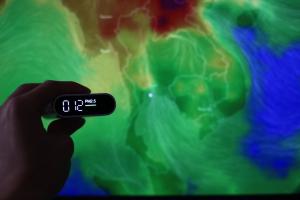

POLLUTION : Les particules fines font le lit de la maladie auto-immune

Actualité publiée le 23/02/2026POLLUTION : Comment elle contribue au diabète et à l’obésité

POLLUTION et DÉMENCE : Les particules fines font des corps de Lewy

Actualité publiée le 13/03/2025POLLUTION : Les particules fines expliquent 30 % du fardeau de l’asthme

POLLUTION : Les particules fines meurtrières même à très faible niveau

Actualité publiée le 01/07/2022POLLUTION URBAINE : 1,8 million de décès supplémentaires chaque année